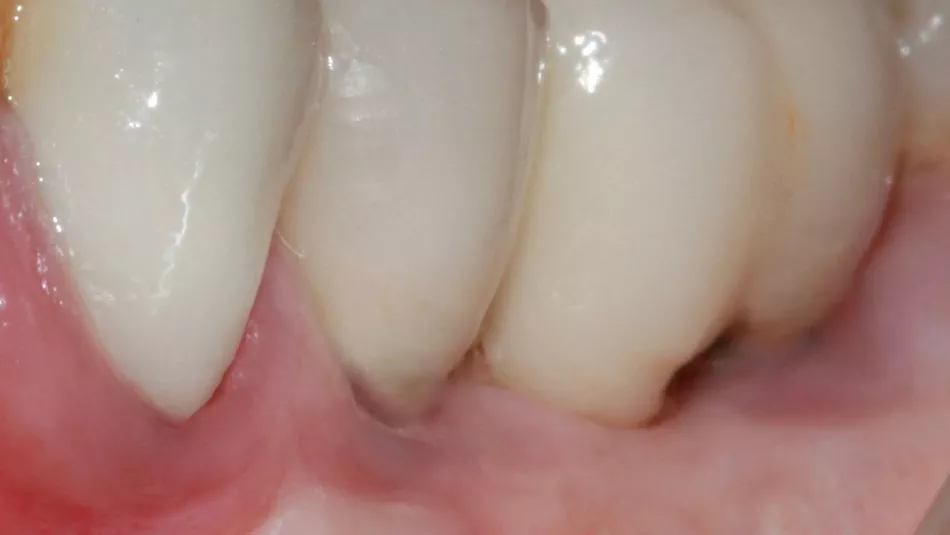

8. 10 days later, satisfactory healing of the mucogingival procedure.

10. Clinical situation 2 years later with the crowns screwed onto the MU abutments (Dr S. Abid, Nice).